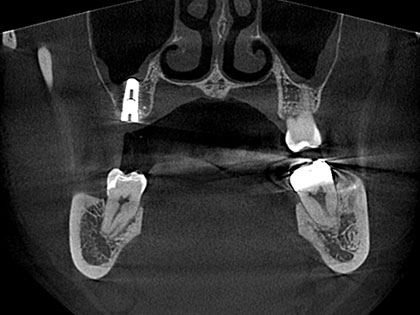

• インプラント術前1

• インプラント術前2